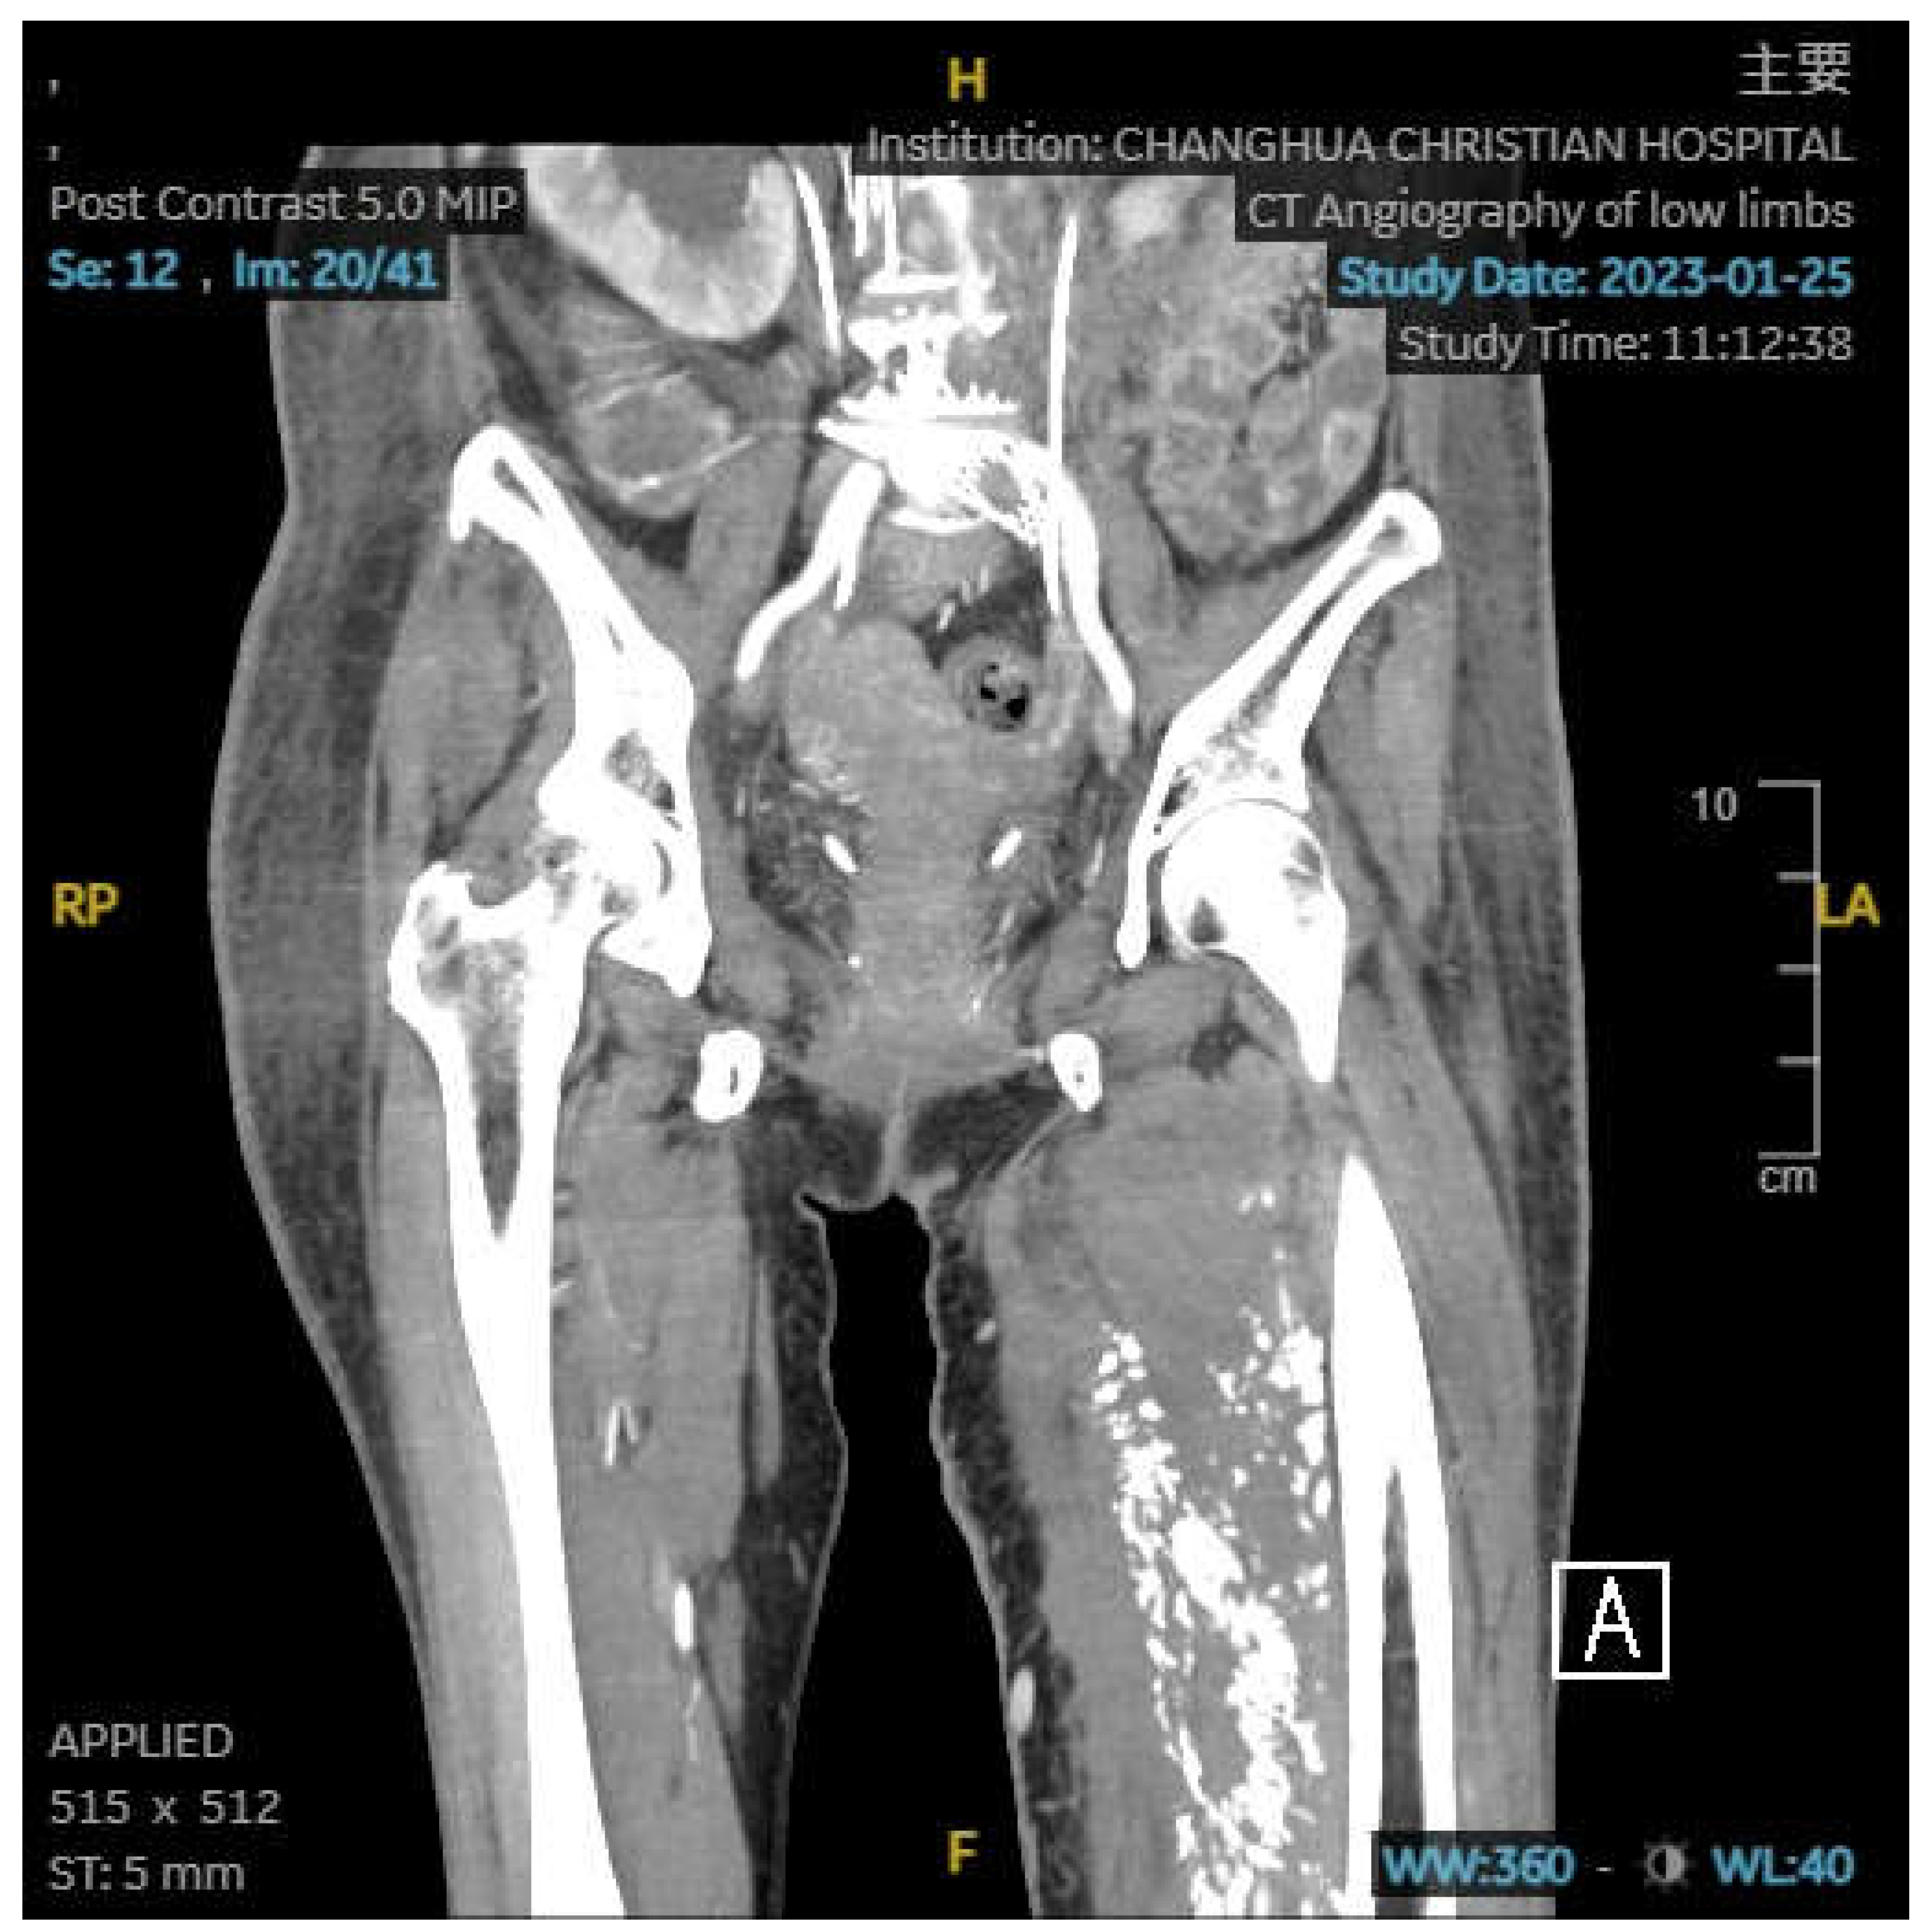

An 66-year-old female has a no medical history. She was presented with diarrhea, change in defecation habit and tenesmus and visited to outpatient department. On rectal examination, a annular mass was palpable at 5 cm from the anal verge. Biopsy from the mass showed adenocarcinoma. Pelvic magnetic resonance imaging and positron emission tomography were ordered and revealed rectal cancer, cT3N2M0. She was received neoadjuvant concurrent radiotherapy and chemotherapy followed by transanal total mesorectal excision with ileostomy. Pathology revealed pT3N2M0, stage III. She regularly visited outpatient department and ileostomy closure was applied after three months later. However, anal pain was complained. Anal nodule was found and biopsy revealed adenocarcinoma. Local recurrence was impressed and laparoscopic abdominoperineal resection was performed. We suggested infusion chemotherapy but she refused. Therefore, she was started on tablet capecitabine. After five months of operation, she complained left leg swelling. Abdominal computed tomography was ordered and it revealed May-Thurner syndrome with left side deep vein thrombosis. (Figure 1) Enoxaparin was prescribed first and rivaroxaban substituted it. Besides, stent was inserted. However, swelling persisted and lower limb computed tomography was ordered again 3 months later. It revealed May-Thurner syndrome post stenting, collapsed left proximal superficial femoral vein related to external compression, and diffuse calcification and area of low density in the left thigh muscle.(Figure 2,3) Computed tomography biopsy was applied and pathology revealed adenocarcinoma. On the other side, she had peritoneal carcinomatosis and intestinal obstruction and ileocecal bypass was performed. Target therapy with chemotherapy was given and she passed away one year later.

Figure 2,3. Abdominal computered tomography revealed diffuse calcification and area of low density in the left thigh muscle. (2) Coronal view (3) Transverse view.